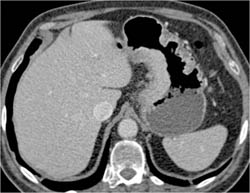

Vanguard Device at Gastroesophageal (GE) Junction for Weight Loss Surgery